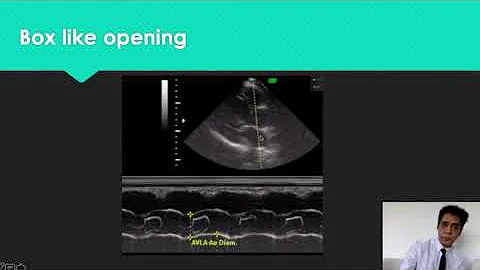

Lv M-mode Measurements #echocardiography #echo #cardiology #ultrasound #cardiachealth #hearthealth